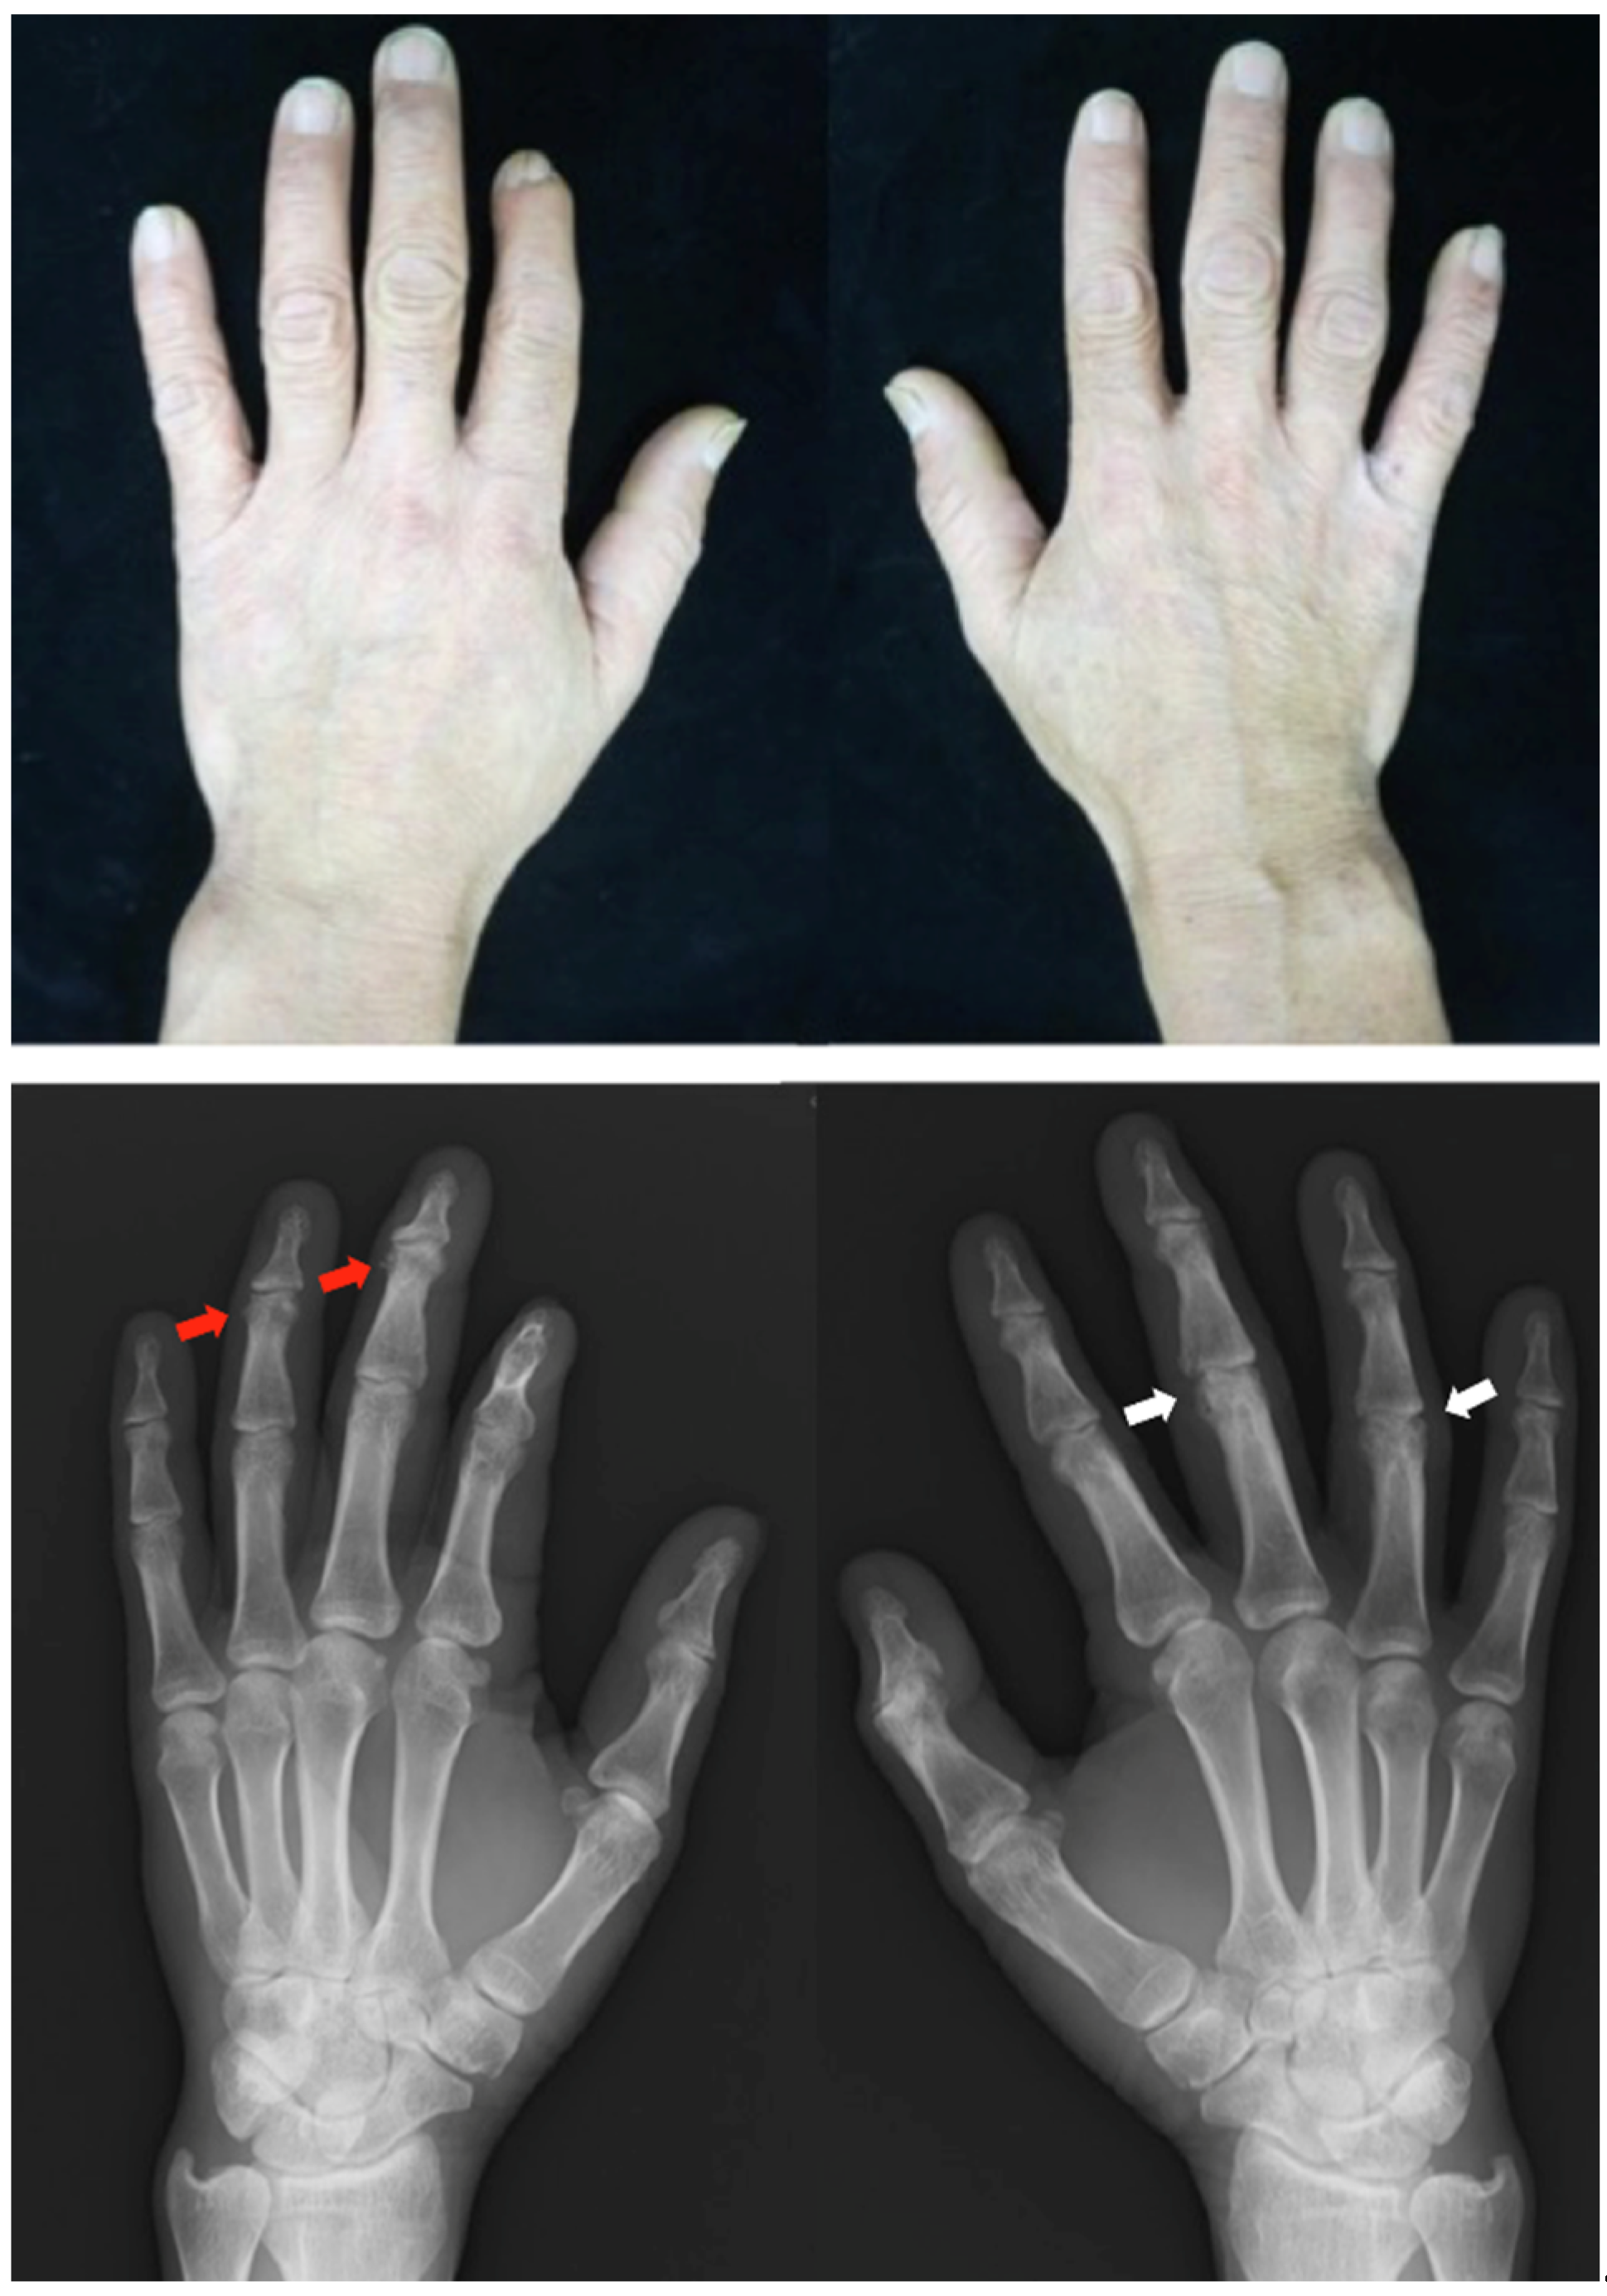

Patient: Woman in her 50s

Patient: Man in his 40s